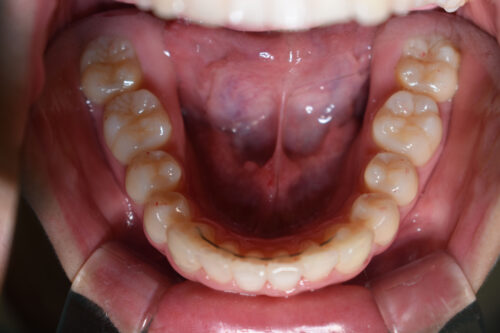

ワイヤー矯正治療7か月後です。

全額矯正治療 88万円、3~4週に一回来院

歯科矯正用アンカースクリュー(デュアル・トップオートスクリュー)上顎左右2本(25000円x1本分 提携医院にて)

ワイヤー期間 7か月, 12回来院

マウスピース型カスタムメイド矯正歯科治療を用いた矯正歯科治療装置を利用した矯正治療 3か月間 33000円、

本症例のように

歯科矯正用アンカースクリュー(デュアル・トップオートスクリュー)を利用し

下顎のオートローテーションを行うことで

歯を抜かない非抜歯矯正治療でも

E-lineを整えることができます。